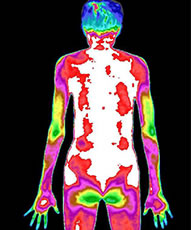

治疗前后炎症对比图/ Inflammation contrast

• 治疗前